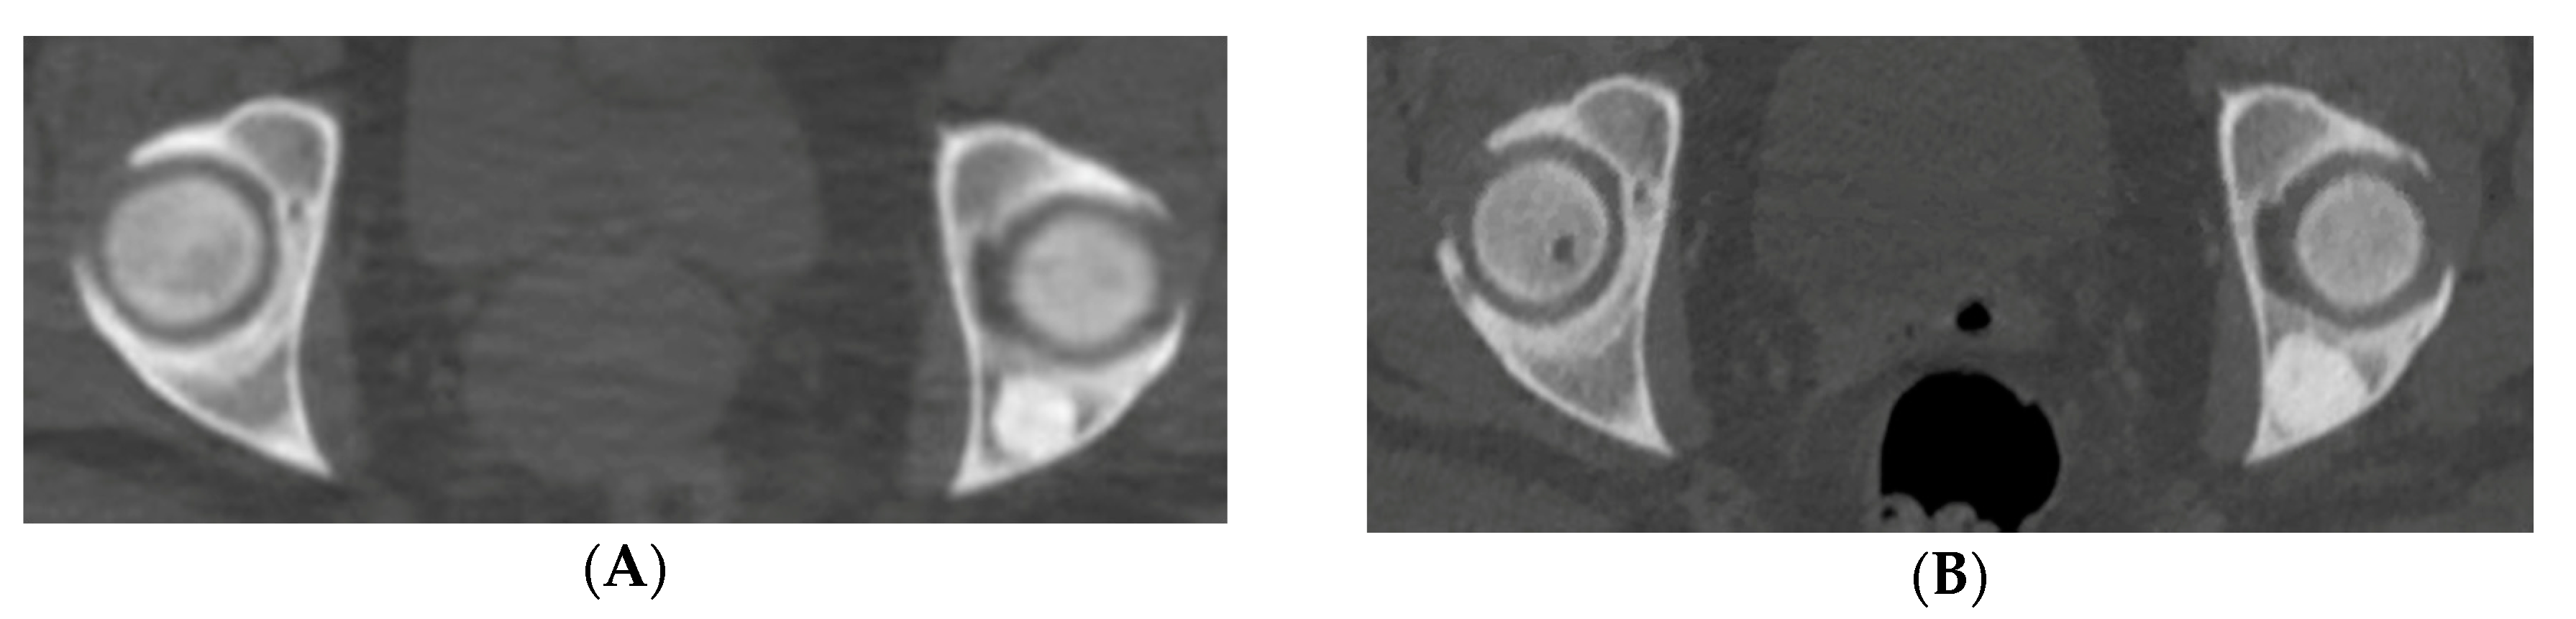

Ten patients with eleven atypical bone islands (ABI) are presented. Among the ten patients, five showed associated pain, seven demonstrated interval enlargement, two had an atypical imaging appearance including one with cortical erosion (Figure 1A,B) and five showed increased activity on BS including one with concurrent enlargement (Figure 2A–C). Mean CT attenuation values ranged from 528 to 1375 Hounsfield Units (HU) with only one BI falling below the proposed 885 HU cutoff [2,3]. Most bone islands were found in the pelvis (7) followed by the femur (3) and vertebrae (1). Most patients were female (eight of the ten cases). Average age was 58.9 years (range—43–87 years). Diagnosis was established clinically in four lesions and by biopsy in seven others. Two atypical BI occurred in the setting of osteopoikilosis. In one of those cases, an atypical area was discovered to be an osteoid osteoma rather than BI. Two of the more unusual cases are presented in detail.